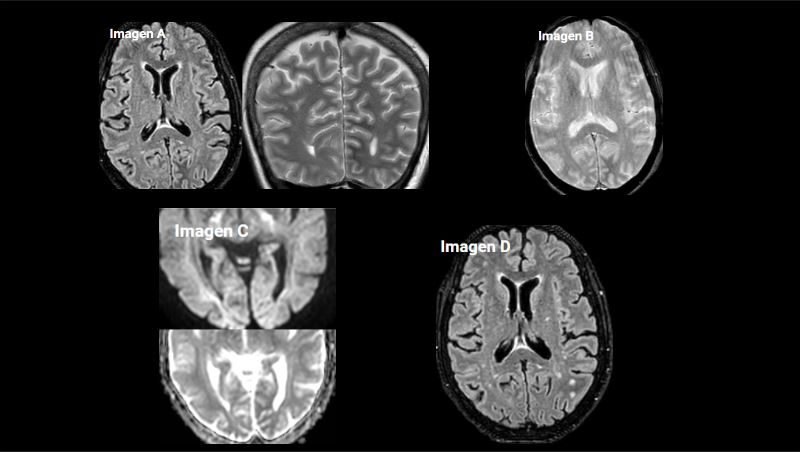

Imagen A. RM craneal secuencia FLAIR axial y T2 coronal. Hipointensidad subcortical difusa, de bordes mal definidos, en la sustancia blanca del lóbulo occipital izquierdo y ligera hiperintensidad cortical.

Imagen B. RM craneal secuencia T2* EG. Hipointensidad de la sustancia blanca del lóbulo occipital izquierdo, sin mostrar artefactos por susceptibilidad magnética, sin restos de hemosiderina.

Imagen C. RM craneal secuencia difusión (factor b= 2500 s/mm²) y mapa ADC, muestra una sutil restricción asociada.

Imagen D. RM craneal secuencia FLAIR axial. Realizada 6 semanas después tras resolución de la hiperglucemia, observando desaparición de los hallazgos visualizados en el estudio previo.